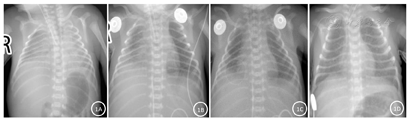

入院胸片提示:两肺充气差、透过度低,呈毛玻璃样,考虑NRDS(Ⅲ期)(图1A)。入院后气管内滴入肺表面活性物质3 h后复查胸片:左肺透过度较前增高,右中下肺野斑片影较前增多,提示右中下肺野感染可能(图1B)。生后9h血氧难以维持90%以上,再次复查胸片:左肺及右上肺野病灶较前吸收减少,右中下肺野感染大致同前(图1C)。生后11h导管前后血氧相差5%以上,查心脏彩超:房间隔缺损(2.5 mm),动脉导管未闭(2.5 mm),三尖瓣轻度返流(PG 26 mmHg),左房稍小。生后8d胸片:双肺透过度较前增高,双肺内病灶较前明显吸收减少(图1D)。住院期间颅腔彩超均未见明显异常。

入院后结合其孕周及出生体重,超低出生体重儿及超未成熟儿诊断明确。气管内滴入肺表面活性物质后,左肺及右上肺野透过度改善,但右中下肺野见大片渗出,结合早破水病史及母亲孕期宫颈分泌物培养异常,考虑先天性肺炎。生后9 h血氧再度下降,需与气胸鉴别,复查胸片与前片相比无明显变化,不支持气胸等。生后11 h,血氧难以维持,且导管前后血氧相差5%以上,需与先天性心脏疾病相鉴别,行床边心脏彩超提示:三尖瓣返流,且此时胸片较前片无明显改变,临床诊断PH。患儿矫正胎龄36周时需经鼻持续气道正压通气支持,根据Jensen 2019 BPD定义,本例患儿BPD分度为Ⅱ级。